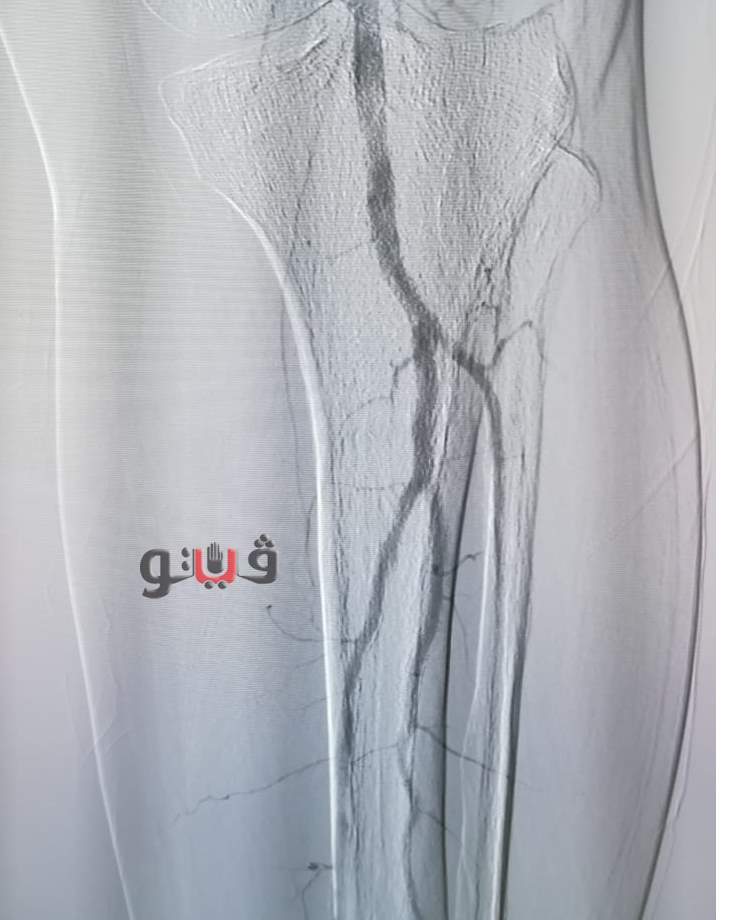

كشف الدكتور سعد مكي وكيل وزارة الصحة بالدقهلية، عن إجراء ثلاث جراحات لحالات تعاني قصورا دمويا حرجا بالشرايين الطرفية تحت الركبة، وذلك داخل وحدة القسطرة الطرفية بمستشفى المنصورة العام الجديد (الدولي) ضمن خطة المستشفى للقضاء على قوائم الانتظار وتقديم خدمة طبية عاجلة لمرضى التأمين الصحي ونفقة الدولة.